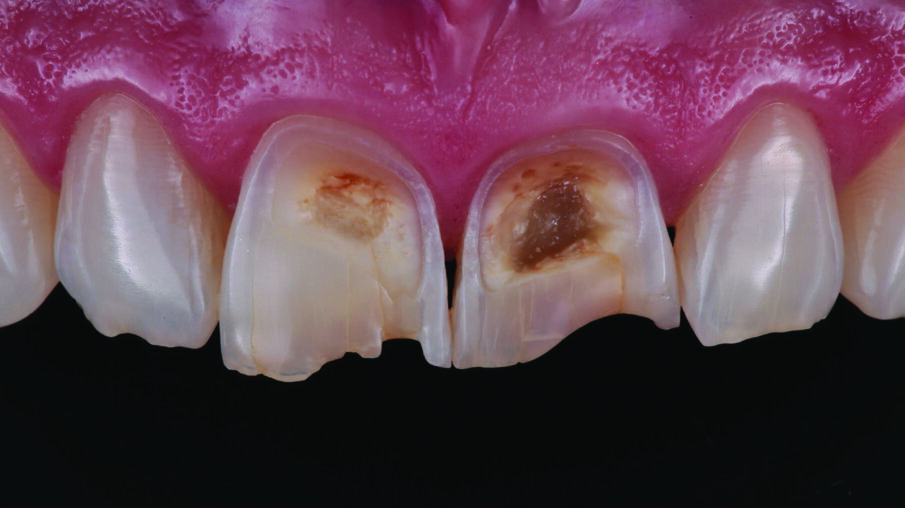

INITIAL SITUATION: Preoperative frontal view of the patient’s teeth, showing severe erosive tooth wear on the vestibular surfaces and incisal edges.

Detailed view of the maxillary incisors. The teeth didn’t show any highly translucent areas, so the use of a single shade/opacity of 3M™ Filtek™ Universal Restorative was selected.

Lateral view of the anterior teeth revealed the depth of the lesions on the vestibular surfaces.